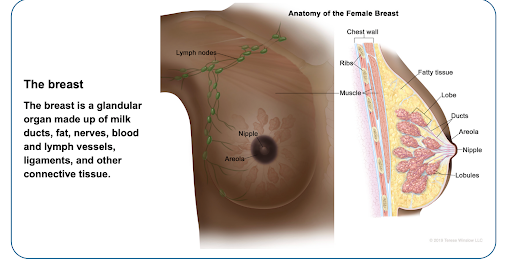

Which part of the body is involved?

Breast cancer usually begins in the breast tissue, particularly in the milk-producing glands (lobules) or the milk-carrying ducts. The breast also contains fatty tissue, connective tissue, blood vessels, and lymphatic vessels, which may be involved as the disease progresses.

Breast cancer usually begins in the breast tissue, particularly in the milk-producing glands (lobules) or the milk-carrying ducts. The breast also contains fatty tissue, connective tissue, blood vessels, and lymphatic vessels, which may be involved as the disease progresses.

Breast cancer develops when normal breast cells undergo changes affecting how they grow, divide, and die. Altered cells can multiply uncontrollably and may accumulate to form a mass. Over time, these cells may spread into nearby tissue or, in some cases, travel via lymphatic channels or blood vessels to other parts of the body.